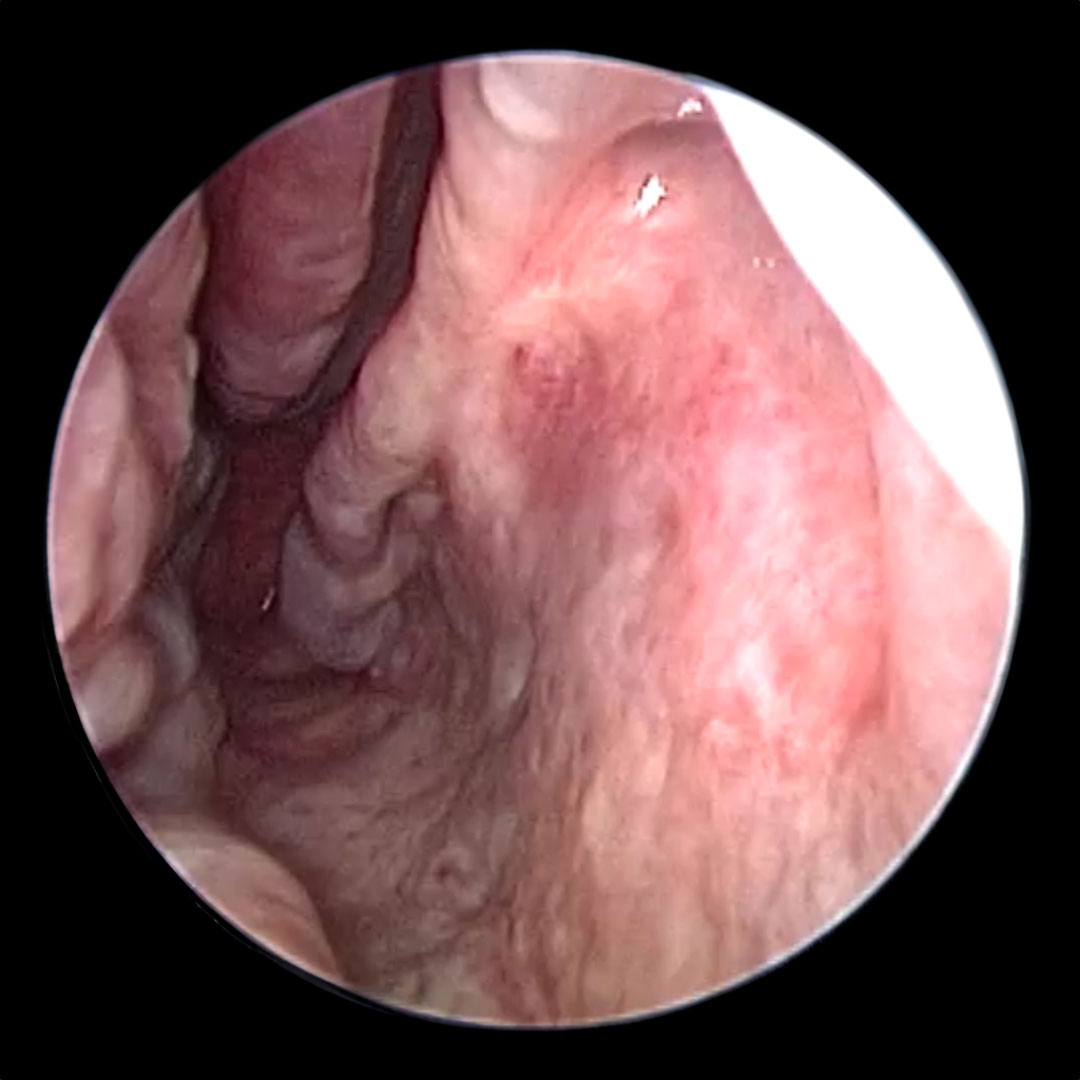

after treatment image Before

before treatment image After